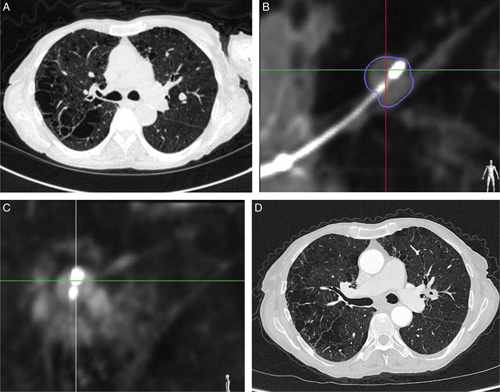

Methods: The prospective, single-arm, 2-center NAVABLATE study (NCT03569111) evaluated transbronchial MWA in patients with histologically confirmed lung malignancies ≤30 mm in maximum diameter who were not candidates for, or who declined, both surgery and stereotactic body radiation therapy. Ablation of 1 nodule was allowed per subject. The nodule was reached with electromagnetic navigation bronchoscopy. Cone-beam computed tomography was used to verify the ablation catheter position and to evaluate the ablation zone postprocedure. The primary end point was composite adverse events related to the transbronchial MWA device through 1-month follow-up. Secondary end points included technical success (nodule reached and ablated according to the study protocol) and technique efficacy (satisfactory ablation based on 1-month follow-up imaging).

Results: Thirty subjects (30 nodules; 66.7% primary lung, 33.3% oligometastatic) were enrolled from February 2019 to September 2020. The pre-procedure median nodule size was 12.5 mm (range 5 to 27 mm). Procedure-day technical success was 100% (30/30), with a mean ablative margin of 9.9±2.7 mm. One-month imaging showed 100% (30/30) technique efficacy. The composite adverse event rate related to the transbronchial MWA device through 1-month follow-up was 3.3% (1 subject, mild hemoptysis). No deaths or pneumothoraces occurred. Four subjects (13.3%) experienced grade 3 complications; none had grade 4 or 5.